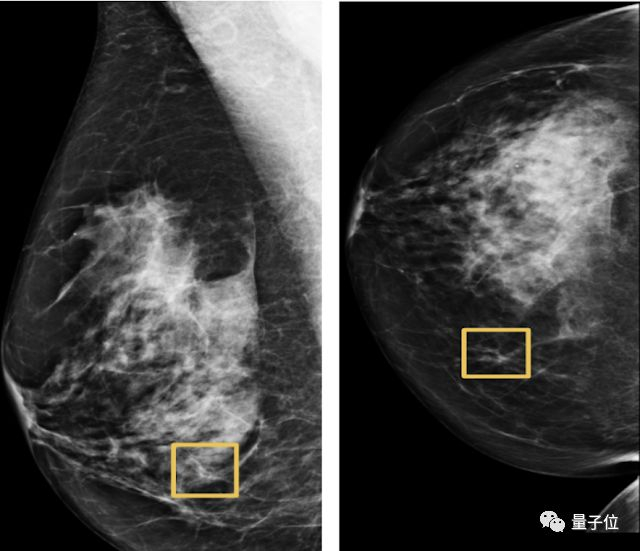

用深度学习模型发现乳腺癌,准确性高于人类专家,降低了诊断中的假阳性和假阴性案例。这项研究不久前刚登上Nature杂志。

相关链接:

谷歌AI乳腺癌检测超过人类,LeCun质疑引起讨论,但平胸妹子可能不适用